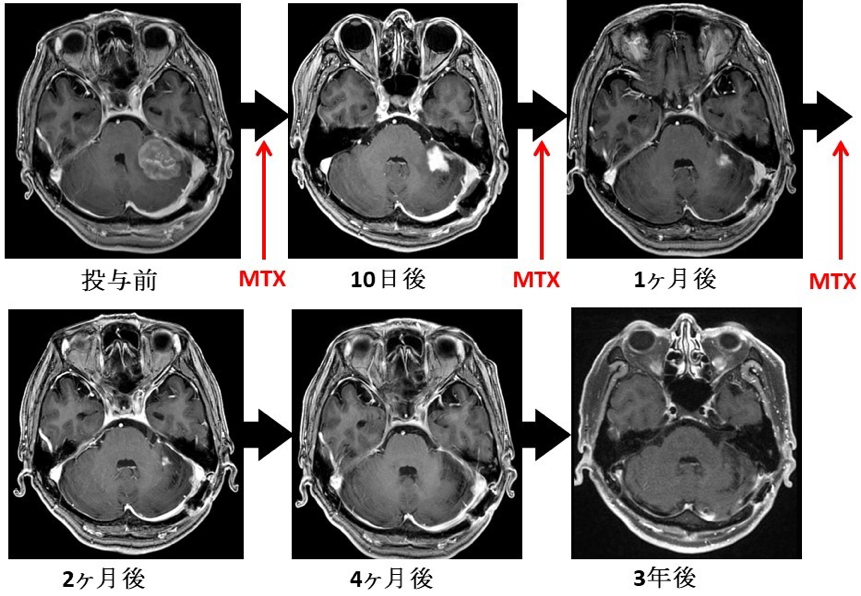

全身性びまん性大細胞型B細胞性悪性リンパ腫の標準治療はR-CHOPと呼ばれる多剤化学療法です。しかし、中枢神経には血液脳関門が存在しているためお薬が脳のなかに入っていかないために、R-CHOP療法は効果に乏しいことから、methotrexate(商品名:メソトレキセート)という抗がん剤を通常量よりも大量に投与して血液脳関門を通過させて治療を行います。

わたしたちは、メソトレキセートを基本として、更に3つの抗腫瘍薬、Rituximab(商品名:リツキサン)、procarbazine(商品名:プロカルバジン)、vincristine (商品名:オンコビン)を用いるR-MPV療法を3-5クール行った後に全脳放射線治療、さらに地固め療法としてCytarabine(シダラビン、別名:Ara-C; 商品名:キロサイド)大量療法(HD-Ara-C)を行っています。これらの治療は血液内科の先生にお願いしております。